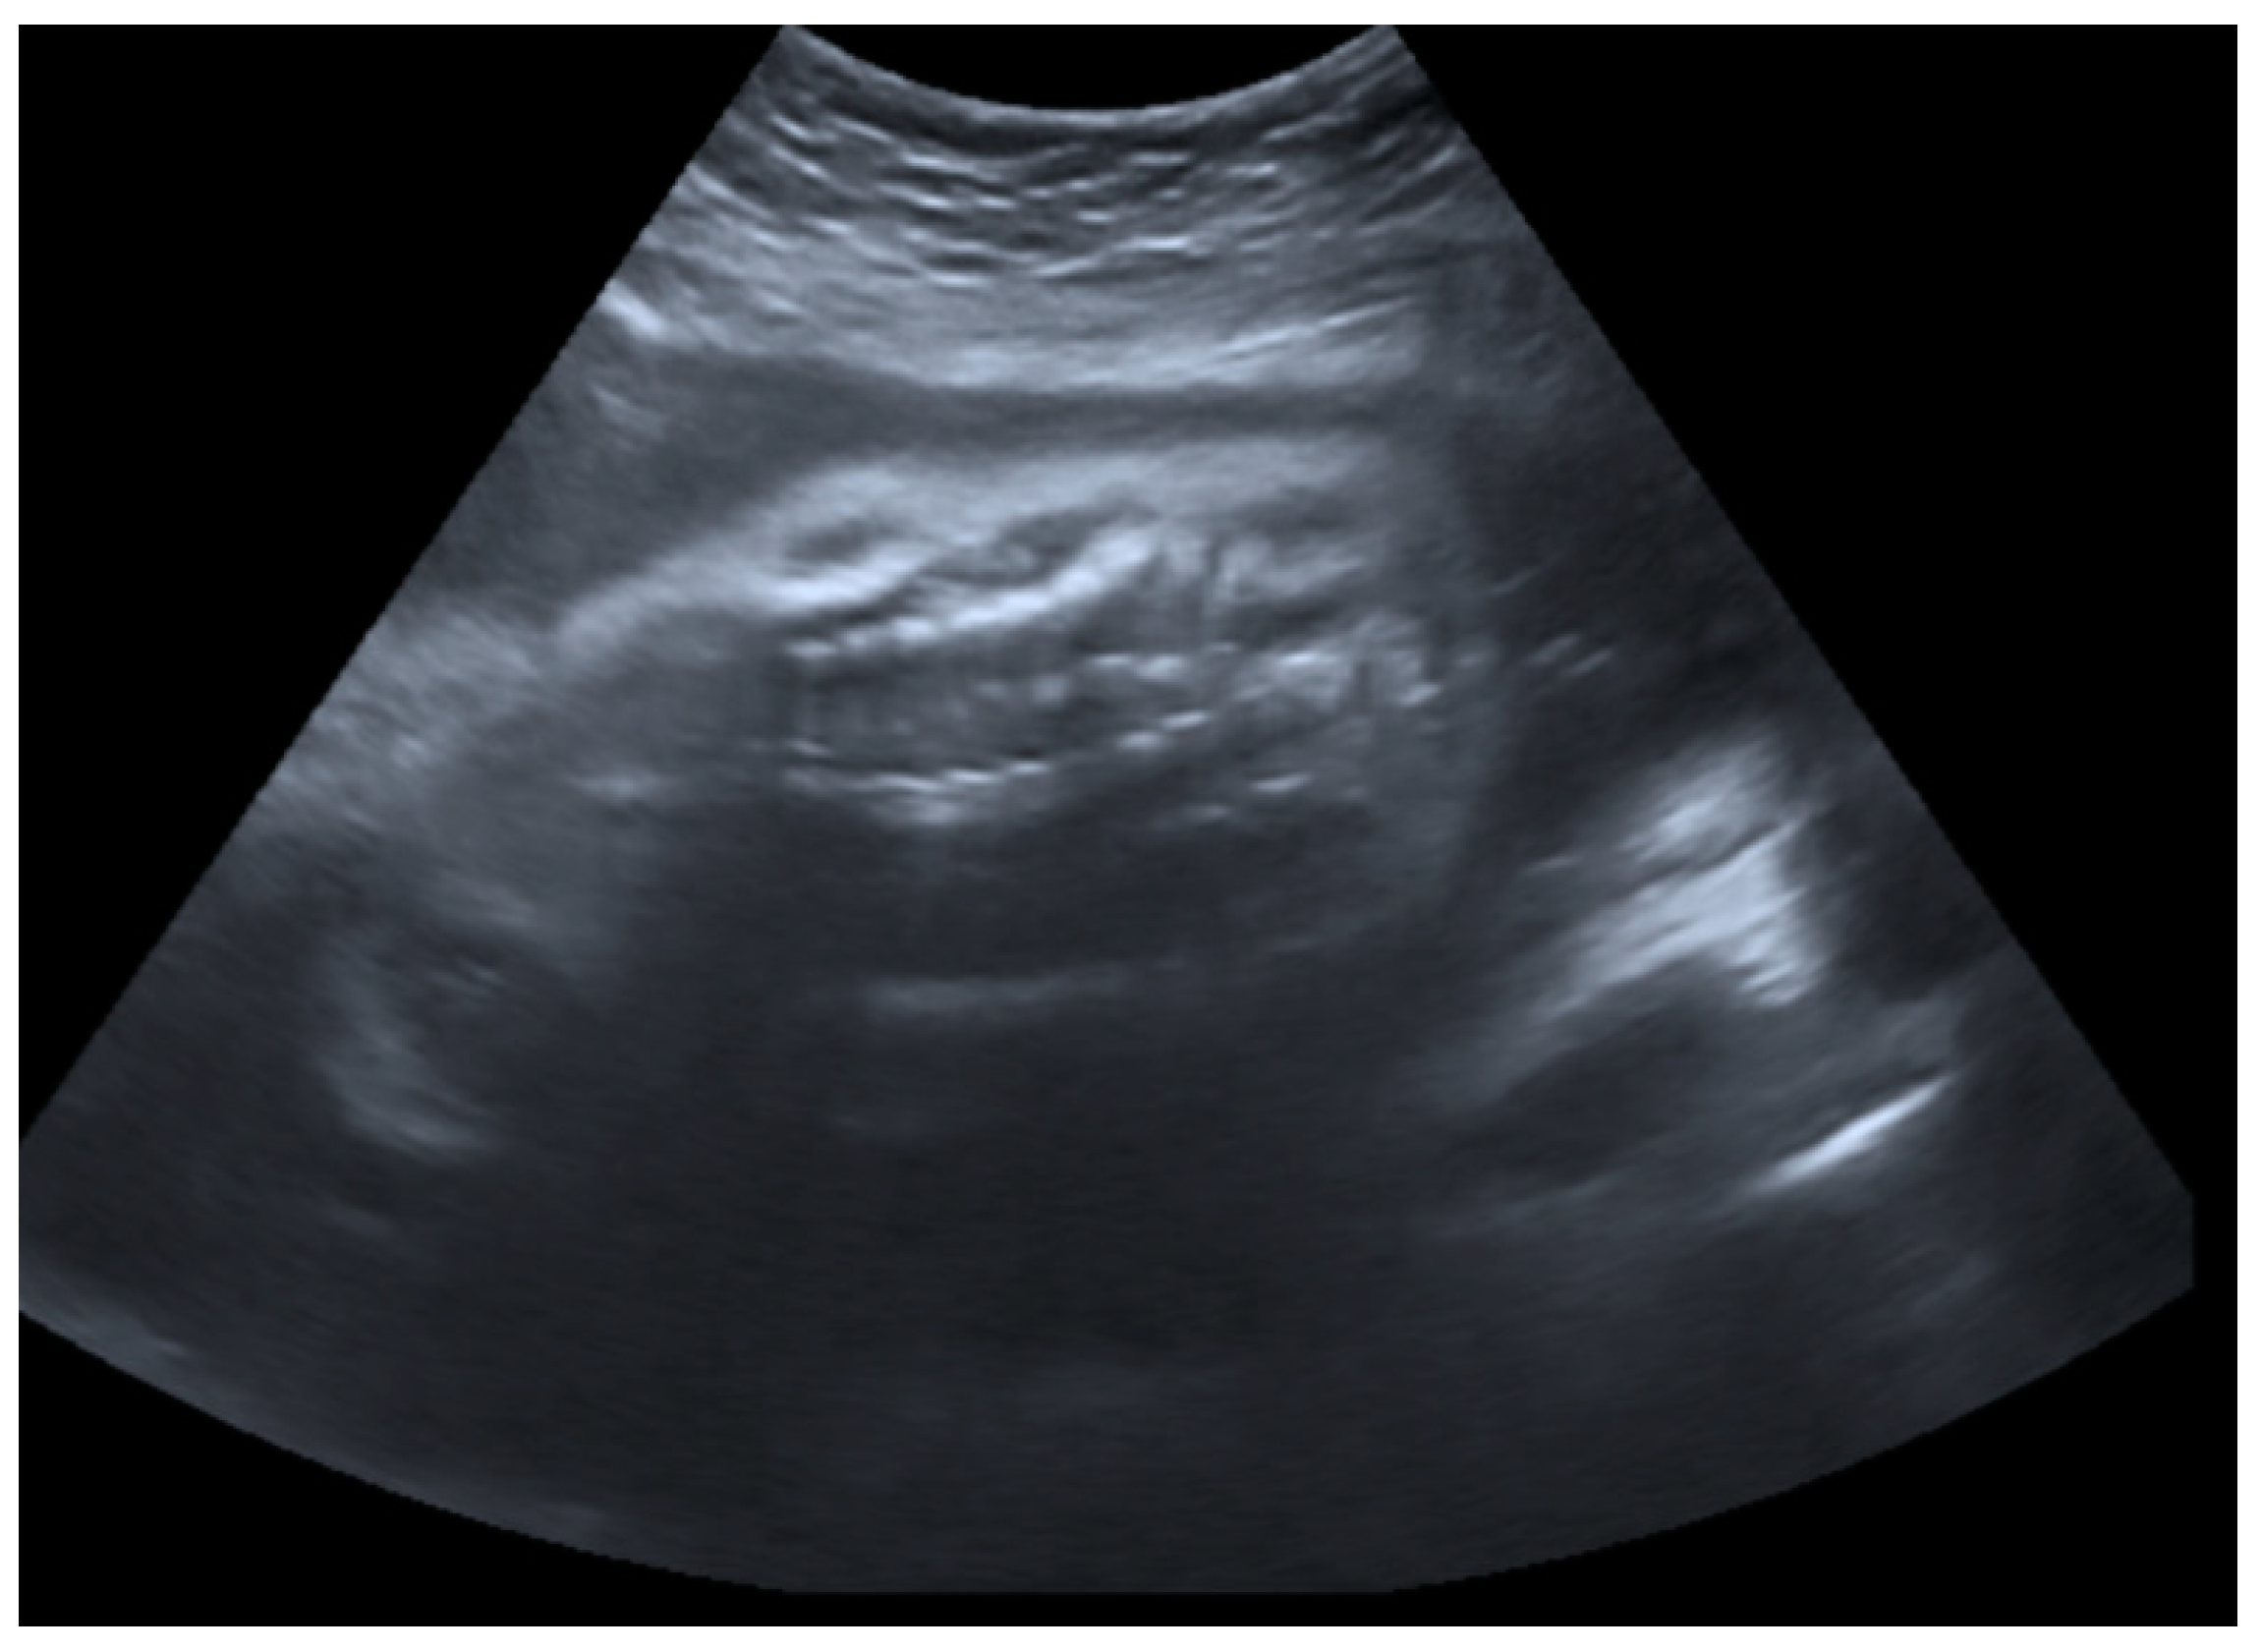

2.1. Prenatal Findings and Further Pregnancy Care